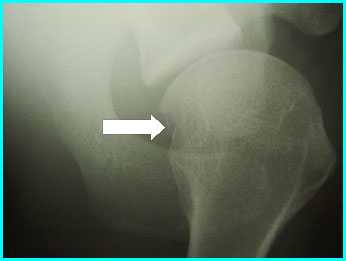

- Рентгенография: [3][19]

- Проекция Граши (передняя проекция) при внутреннем и внешнем повороте; транскапулярная проекция (рентгеновские лучи каудально от стандартной передней проекции); аксиллярная проекция с как можно большим внешним поворотом и проекция West-Point (если позволяет боль)

- Важный первый шаг при эффективной оценке гленогумеральных связок, а также костной патологии плечевой кости и гленоида

- Можно обнаружить костные поражения, связанные с нестабильностью плеча

- Трудно увидеть поражение Хилла-Сакса

- Обнаружение и локализация компрессионного перелома

- Экономичное, минимальное воздействие излучения, удобное для пациента

- Поражение Хилла-Сакса: Явное трехгранное углубление в контуре плечевой кости [4]

Ямка на задней поверхности головки является дефектом Хилл-Сакса и образуется из-за соударения о передний край гленоидальной впадины при периодически повторяющихся вывихах.

На КТ в формате 3D реконструкции на задней поверхности головке видно углубление-дефект Хилл-Сакса

На рентгенограммах в аксиллярной проекции также виден на головке дефект Хилл-Сакса